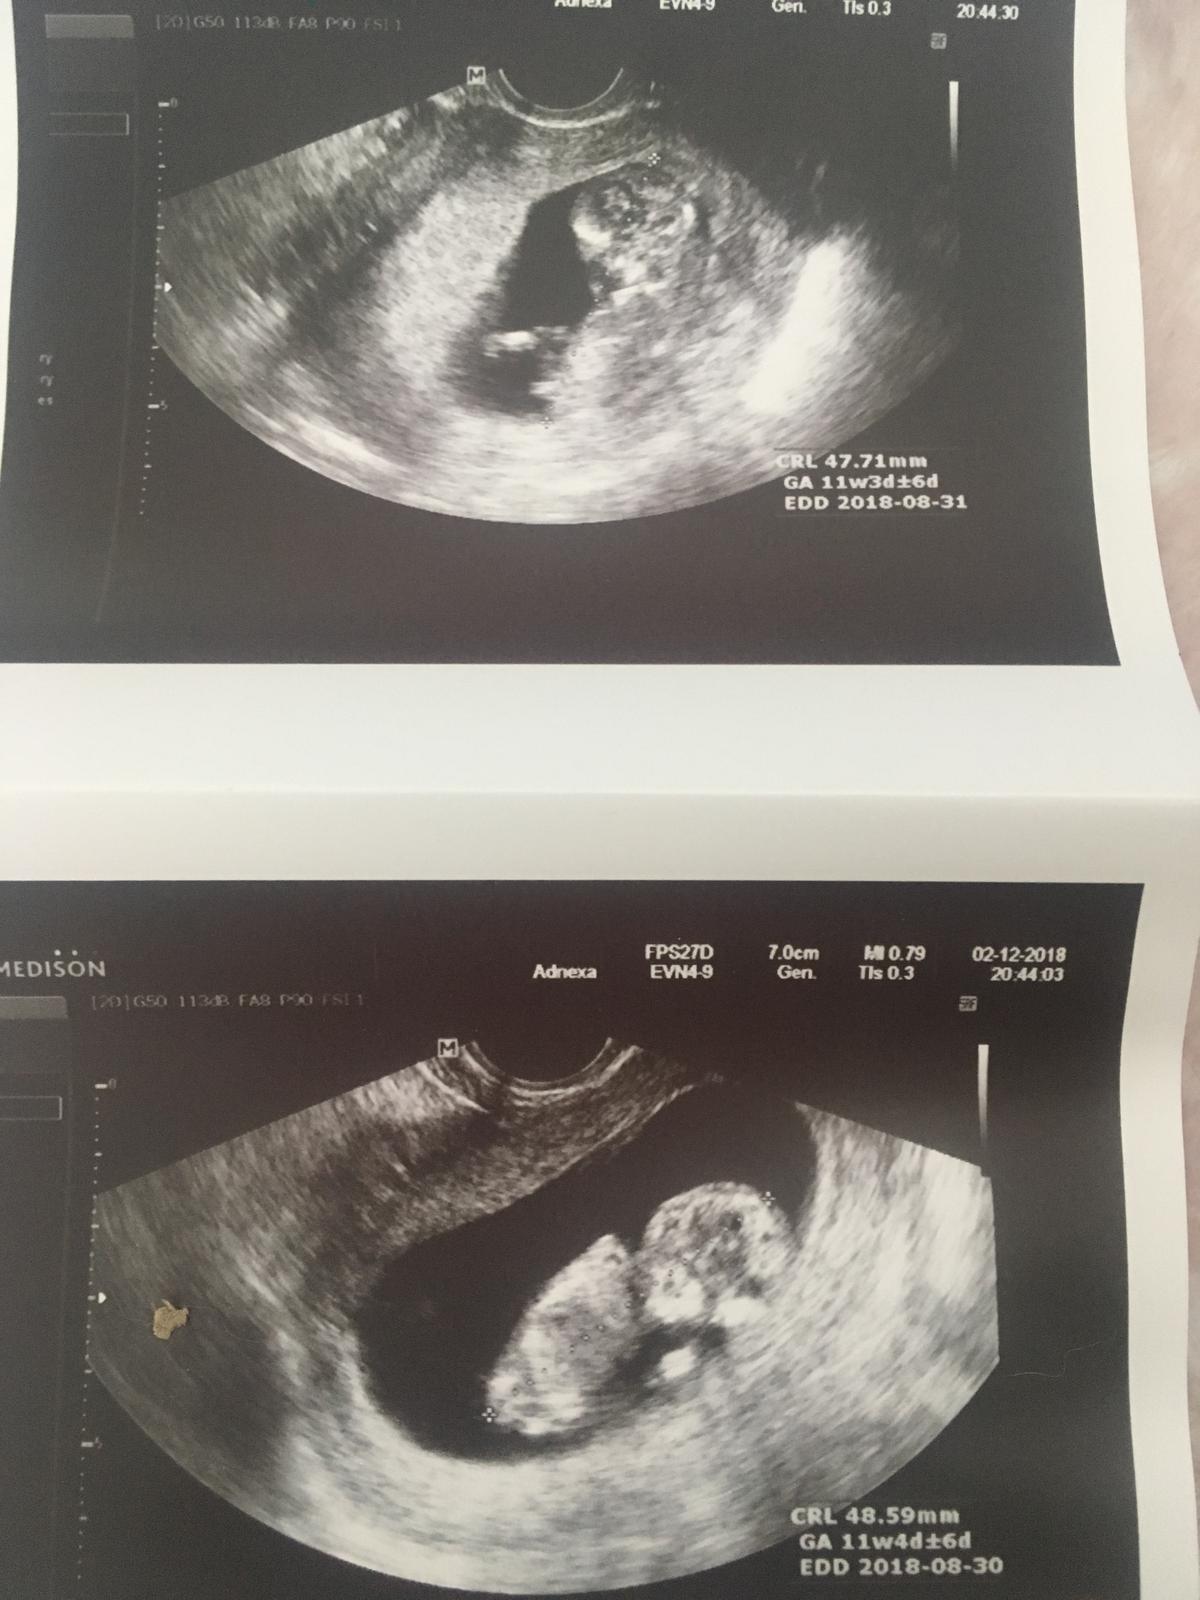

Termín porodu v srpnu 2018

Přidávám se 🙂 dneska na utz vše ok a termín mám 19.8. 🙂

U nás na posledním UTZ téměř 8cm,TP 11.8. 🙂